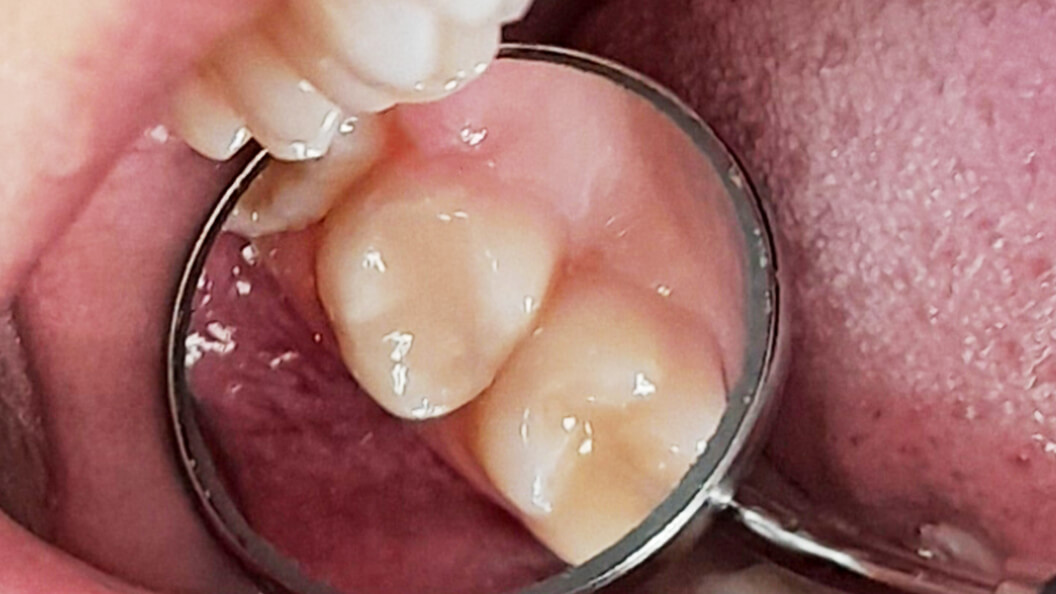

Пациентка обратилась в «Стоматологию Комфорта» с жалобами на кратковременную боль от холодного в области 17 зуба. Врач-стоматолог-терапевт Похилько Надежда Геннадьевна в ходе осмотра выявила кариозную полость на окклюзионной поверхности 17 зуба. Зондирование было болезненно, перкуссия — безболезненна. После препарирования под контролем кариес-маркера был поставлен диагноз: глубокий кариес окклюзионной поверхности 17 зуба. Врач пришёл к выводу о лечении с последующей установкой пломбы из светоотверждаемого композита Estelite.

- постановка пломбы из светоотверждаемого композита Estelite;